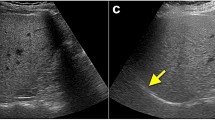

Quantification of LFC in each region of interest

MR imaging results were interpreted by consensus by two radiologists, who were blinded to the 1H-MRS findings. On the low T1-weighted triple-echo gradient-echo sequence and for each patient, we drew a 2D region of interest (ROI) measuring 2-3 cm in diameter in each hepatic segment on three successive slices (Fig 1). Signal intensity in each ROI was recorded for IP1 (TE = 2.46 ms), OP (TE = 3.69 ms) and IP2 (TE = 4.92 ms) of the triple-echo sequence. We used the “copy and paste” function of the workstation (Leonardo; Siemens, Erlangen, Germany) to draw exactly the same ROIs at the same locations on the IP and OP images. The signal intensity for each segment was obtained by averaging the signal intensity in the corresponding ROIs of the three successive slices. The signal intensity recorded for the left liver was obtained by averaging the signal intensity of the ROIs drawn in segments II, III and IV, whereas the signal intensity for the right liver was obtained by averaging the signal intensity of the ROIs in segments V, VI, VII and VIII. Fat fraction values were calculated as previously reported [7].

where SIOP was OP signal intensity. The problem of fat-water ambiguity due to chemical-shif gradient-echo imaging is not relevant when assessing liver steatosis, since many 1H-MRS studies [1, 7, 11, 17] support the hypothesis that steatosis exceptionally exceeds 50 %. A total of 968 fat fractions were recorded in the 121 patients of our study. To visually check the validity of the fat fractions in each ROI, a fat map was built from basic image calculation functions of the workstation [11].